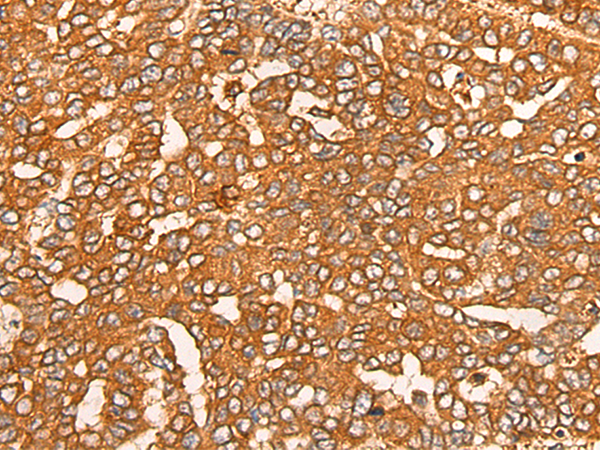

IHC positive control: |

Human liver cancer |